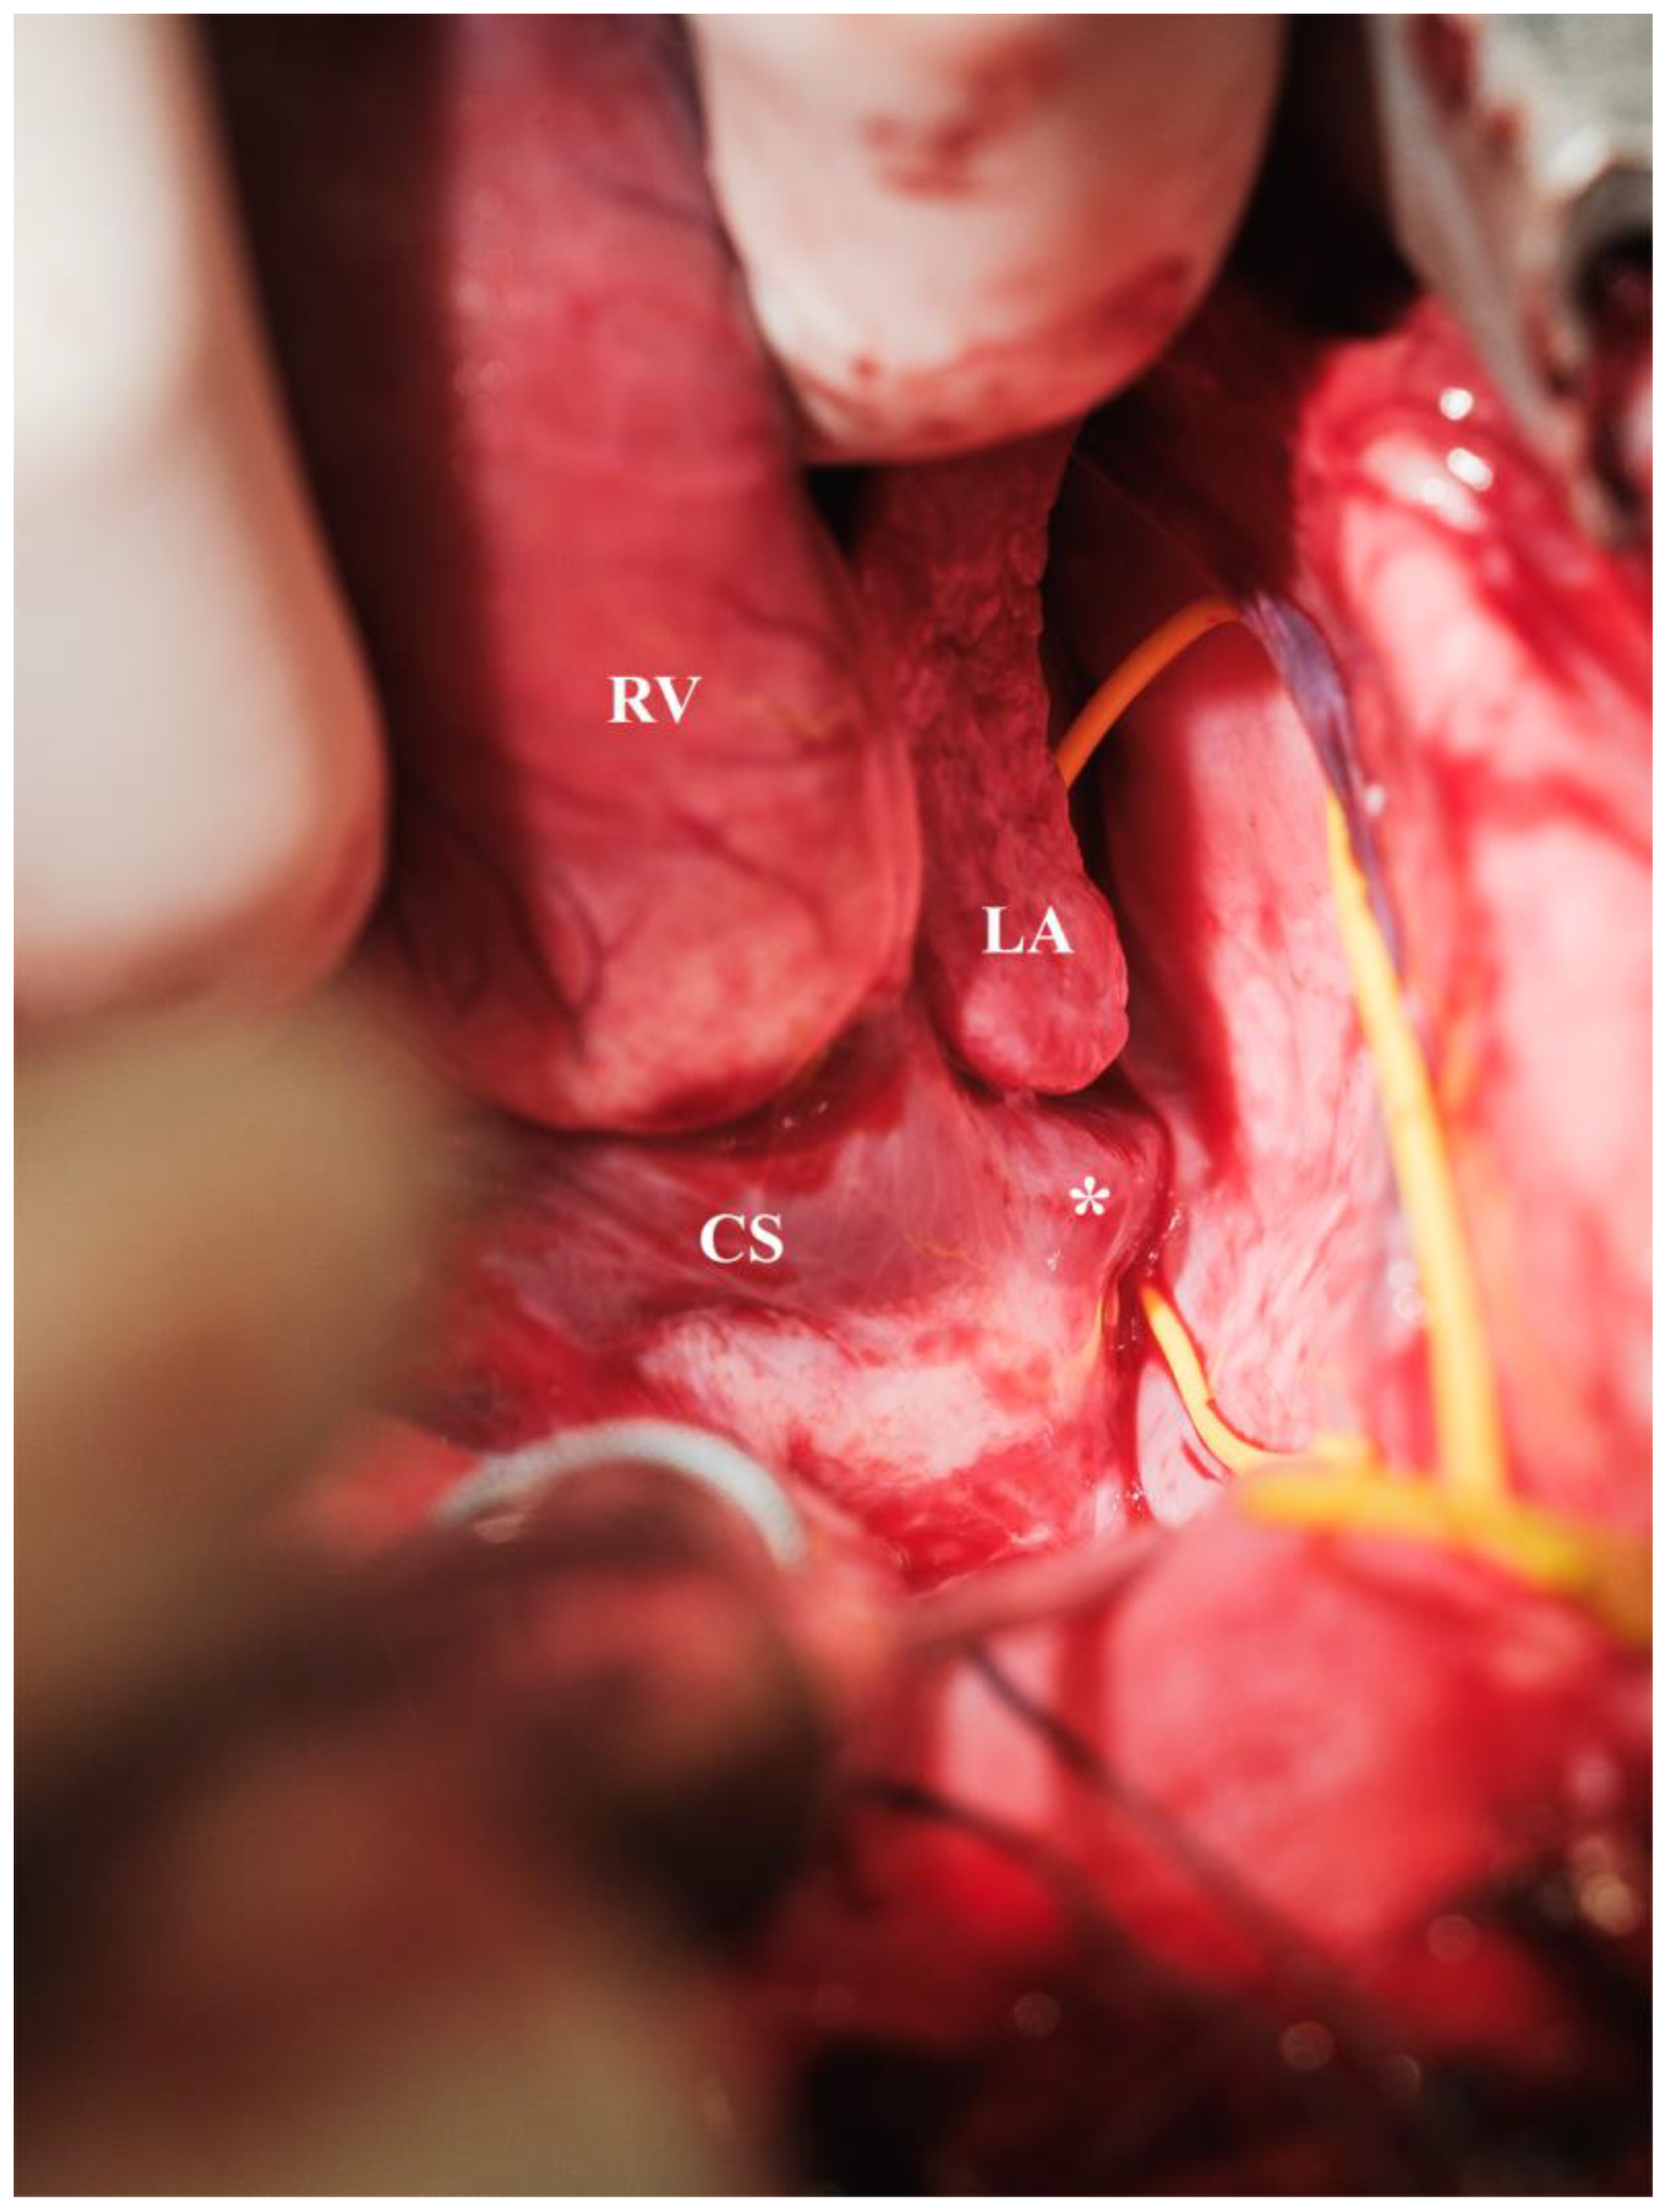

| CS | coronary sinus |

| LA | left atrium |

| RV | right ventricle |